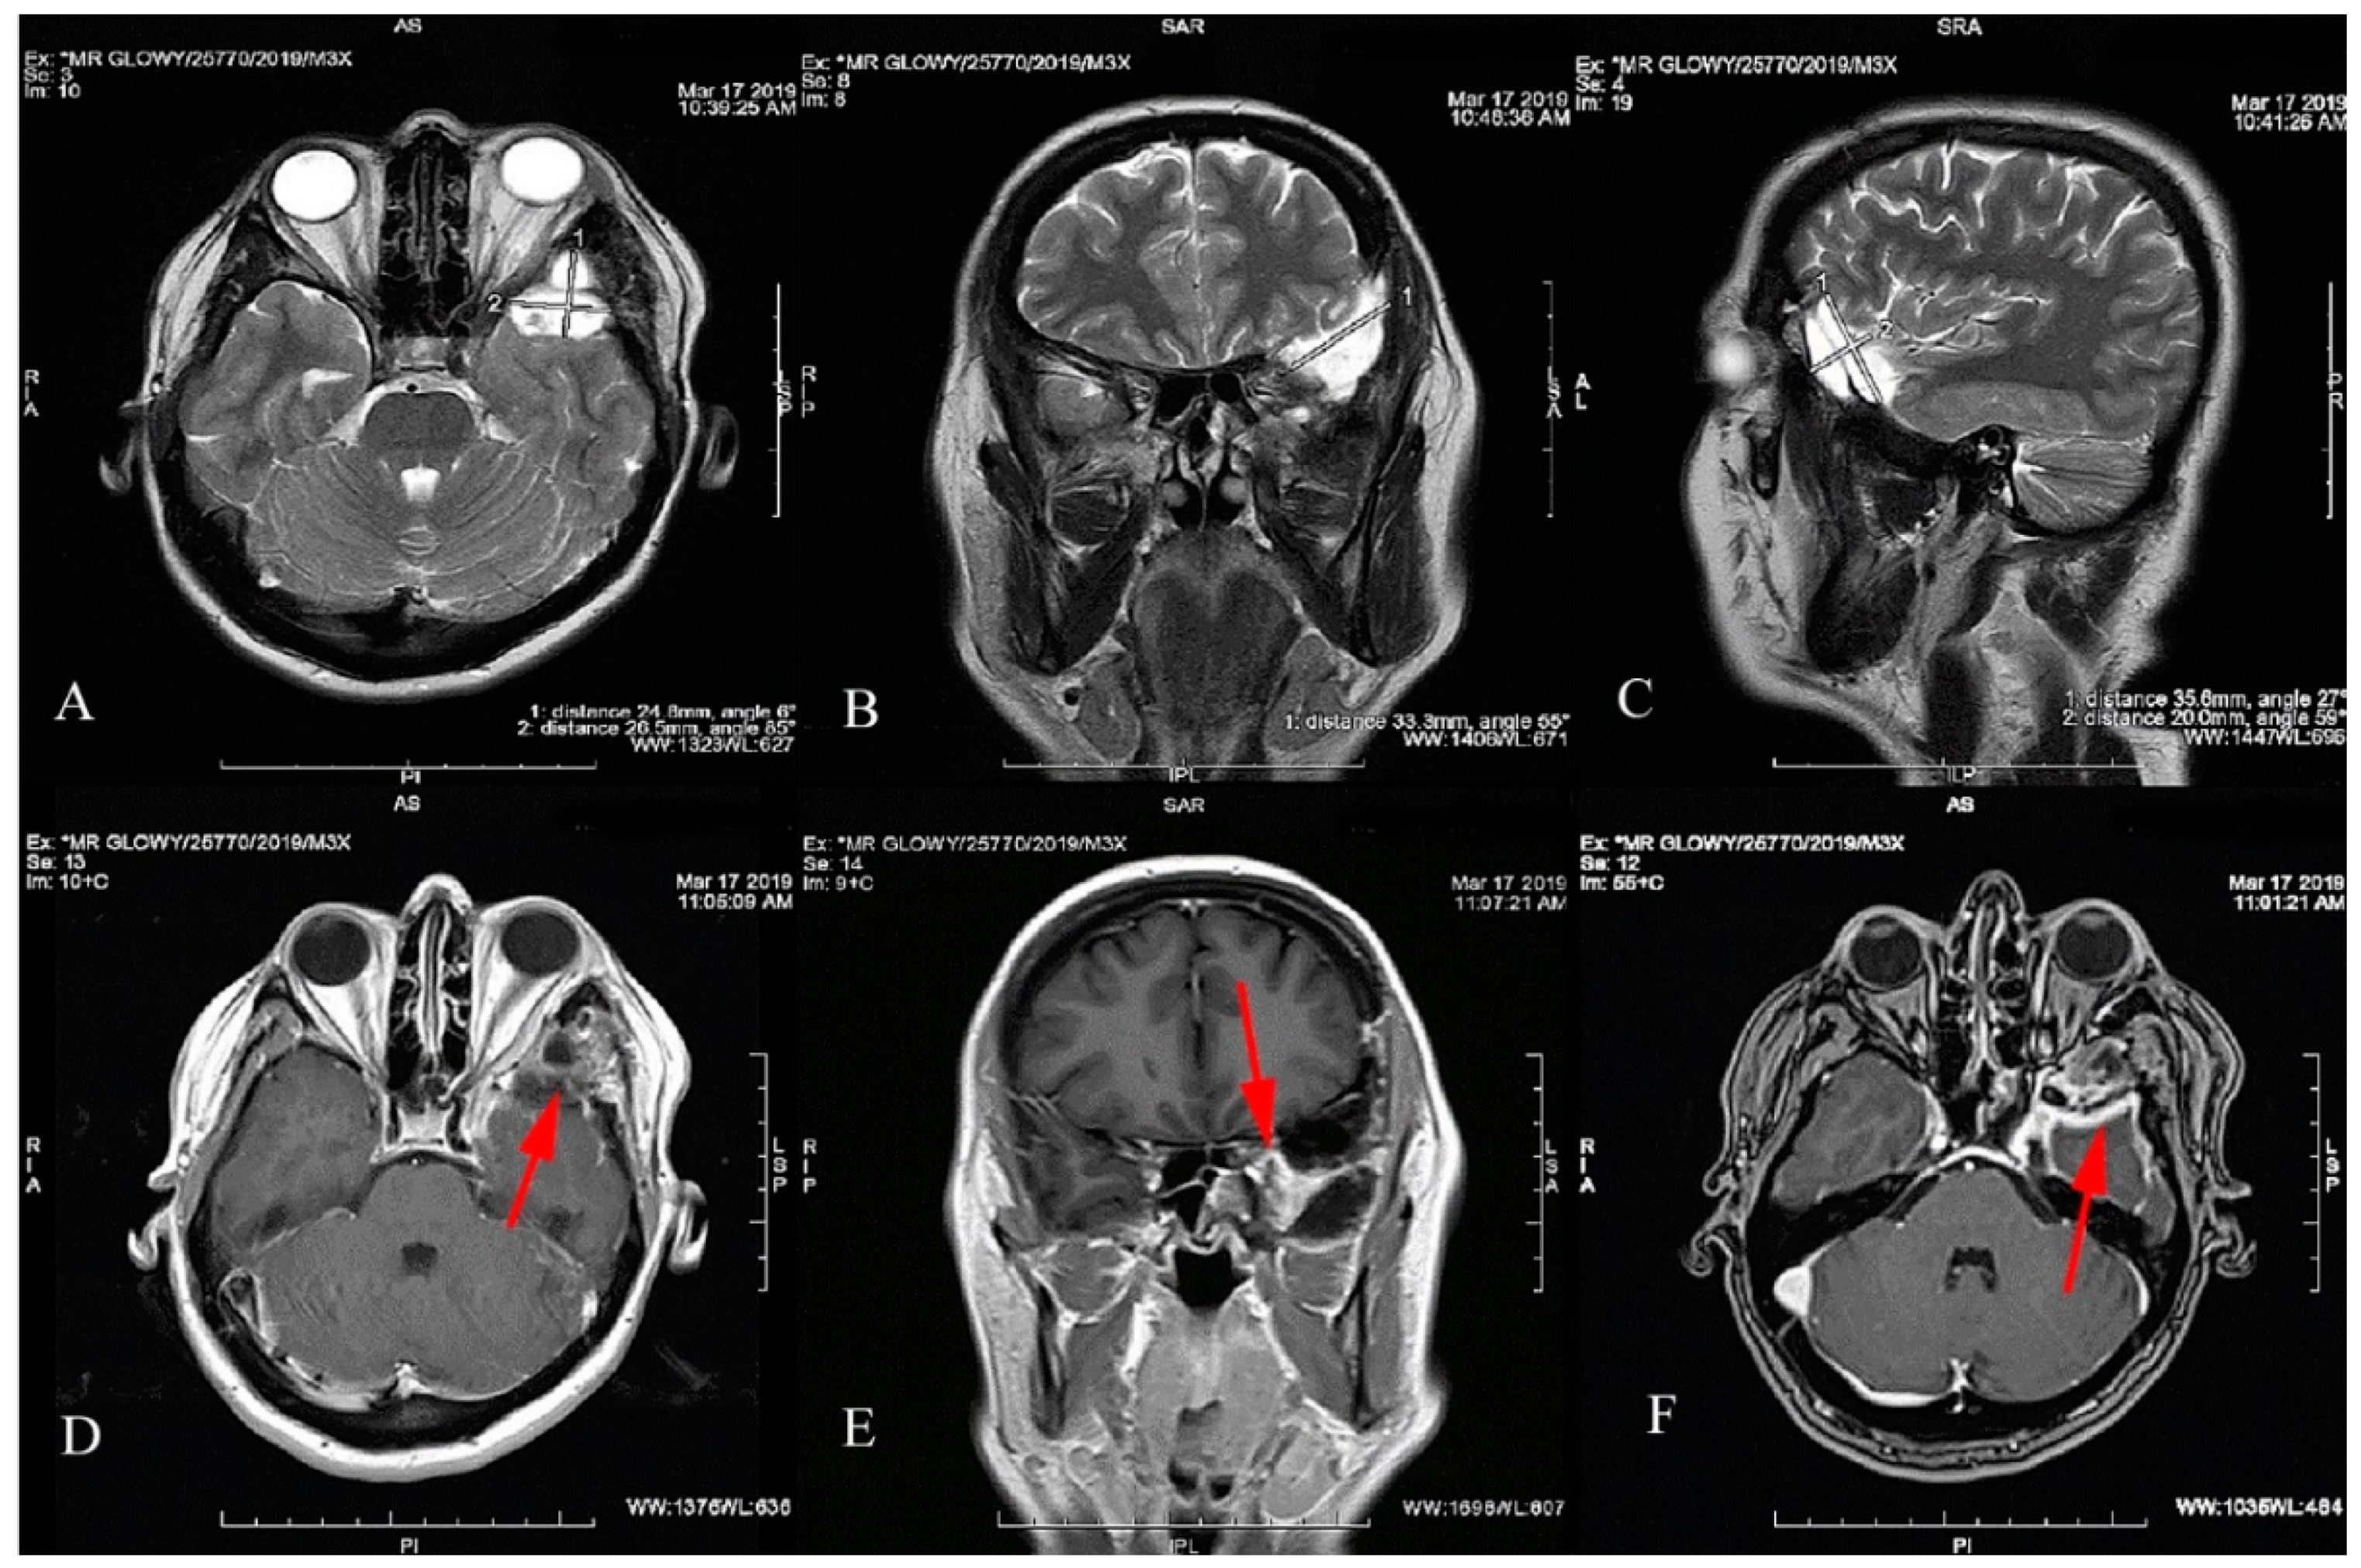

2. Case Report